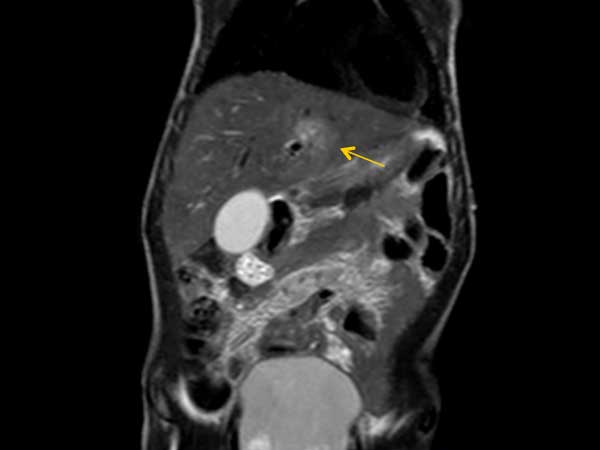

Coronal T2w TSE (with Resp. Navigator)